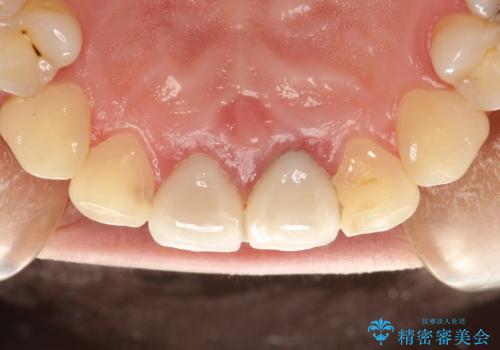

開始前

-